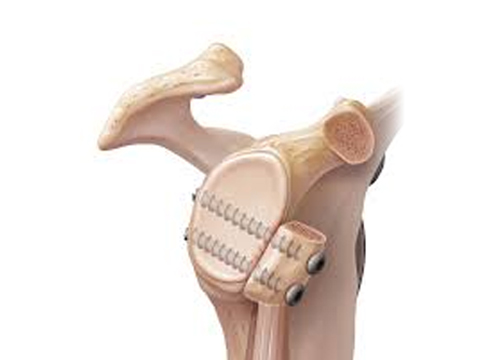

Luxação acrômio-clavicular

Ocorre frequentemente em traumatismos quando o paciente cai sobre o ombro. Comum em esportes como judô, ciclismo e futebol. A articulação entre a clavícula e o acrômio é estabilizada por dois conjuntos de ligamentos: um entre o acrômio e a clavícula e outro entre a clavícula e o processo coracoide. A luxação acromioclavicular pode ser […]